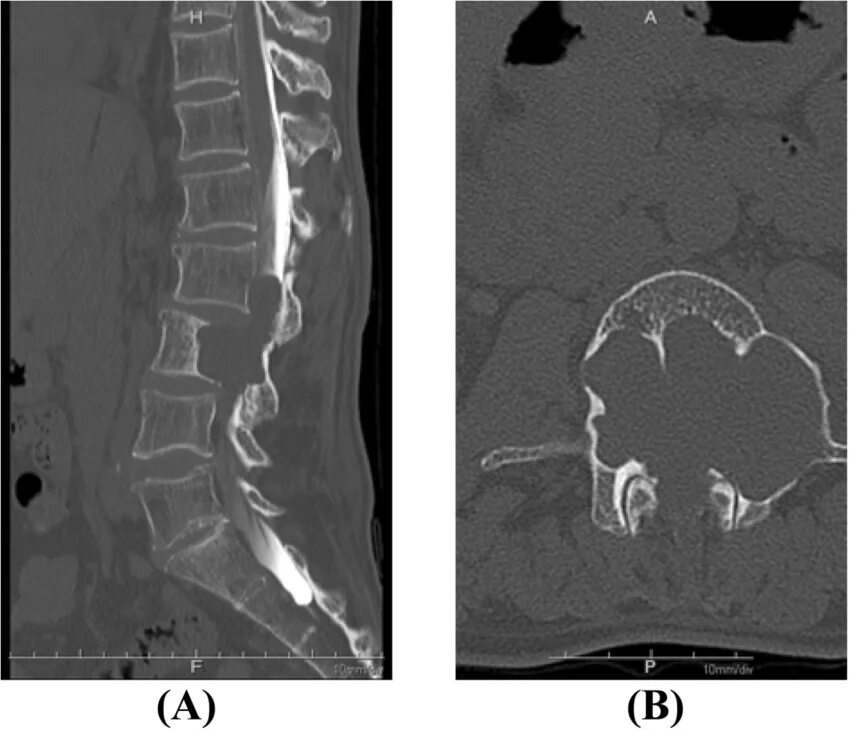

Pre operation